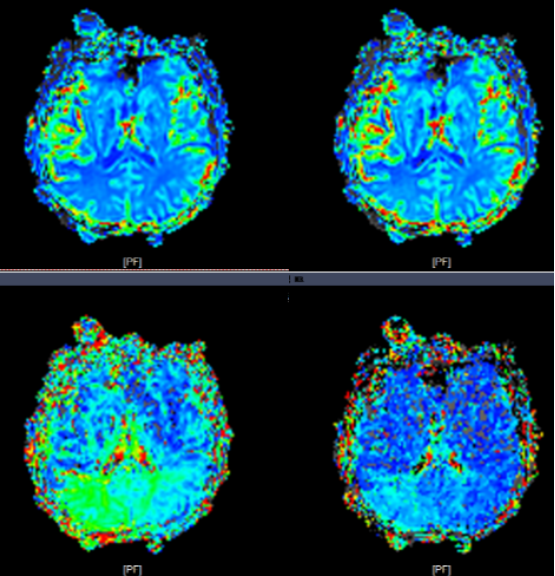

患者再次入院后,郝永岗教授等专家合作完成苏州市首例术中磁共振指导下的症状性颅内动脉狭窄支架植入术。此次手术充分利用我院复合手术室(DSA+MRI双杂交)的优势,有效提高了手术的安全性和有效性。术后即刻行MRI-PWI显示:责任血管供血区血流灌注较前明显改善,提示支架精准定位释放。

术前PWI:右侧岛叶、颞叶、右侧脑室旁及放射冠区CBF、CBV减低,MTT、TTP较对侧延长

术后PWI:右侧岛叶、颞叶、右侧脑室旁及放射冠区血流明显改善